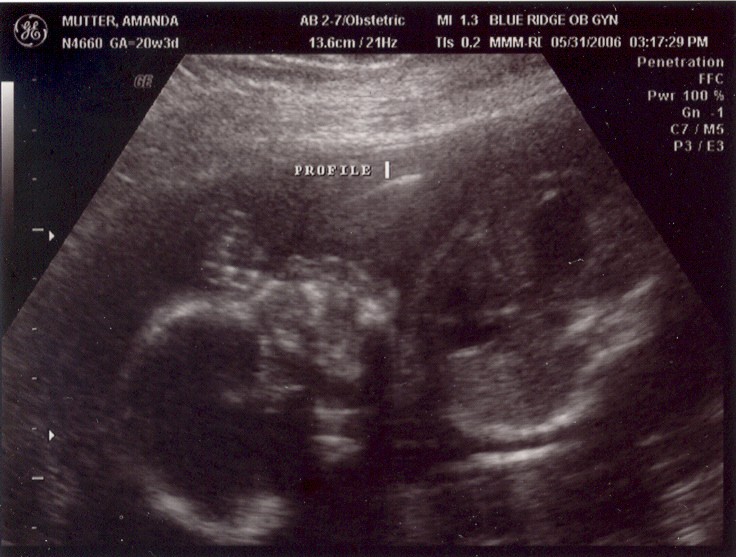

May 31, 2006: Diagnostic Ultrasound

OBs regularly do these to check if babies have all the right number of arms, brains, etc.

It's a girl! After getting this picture, my parents got to stop researching boys' names and circumcision.